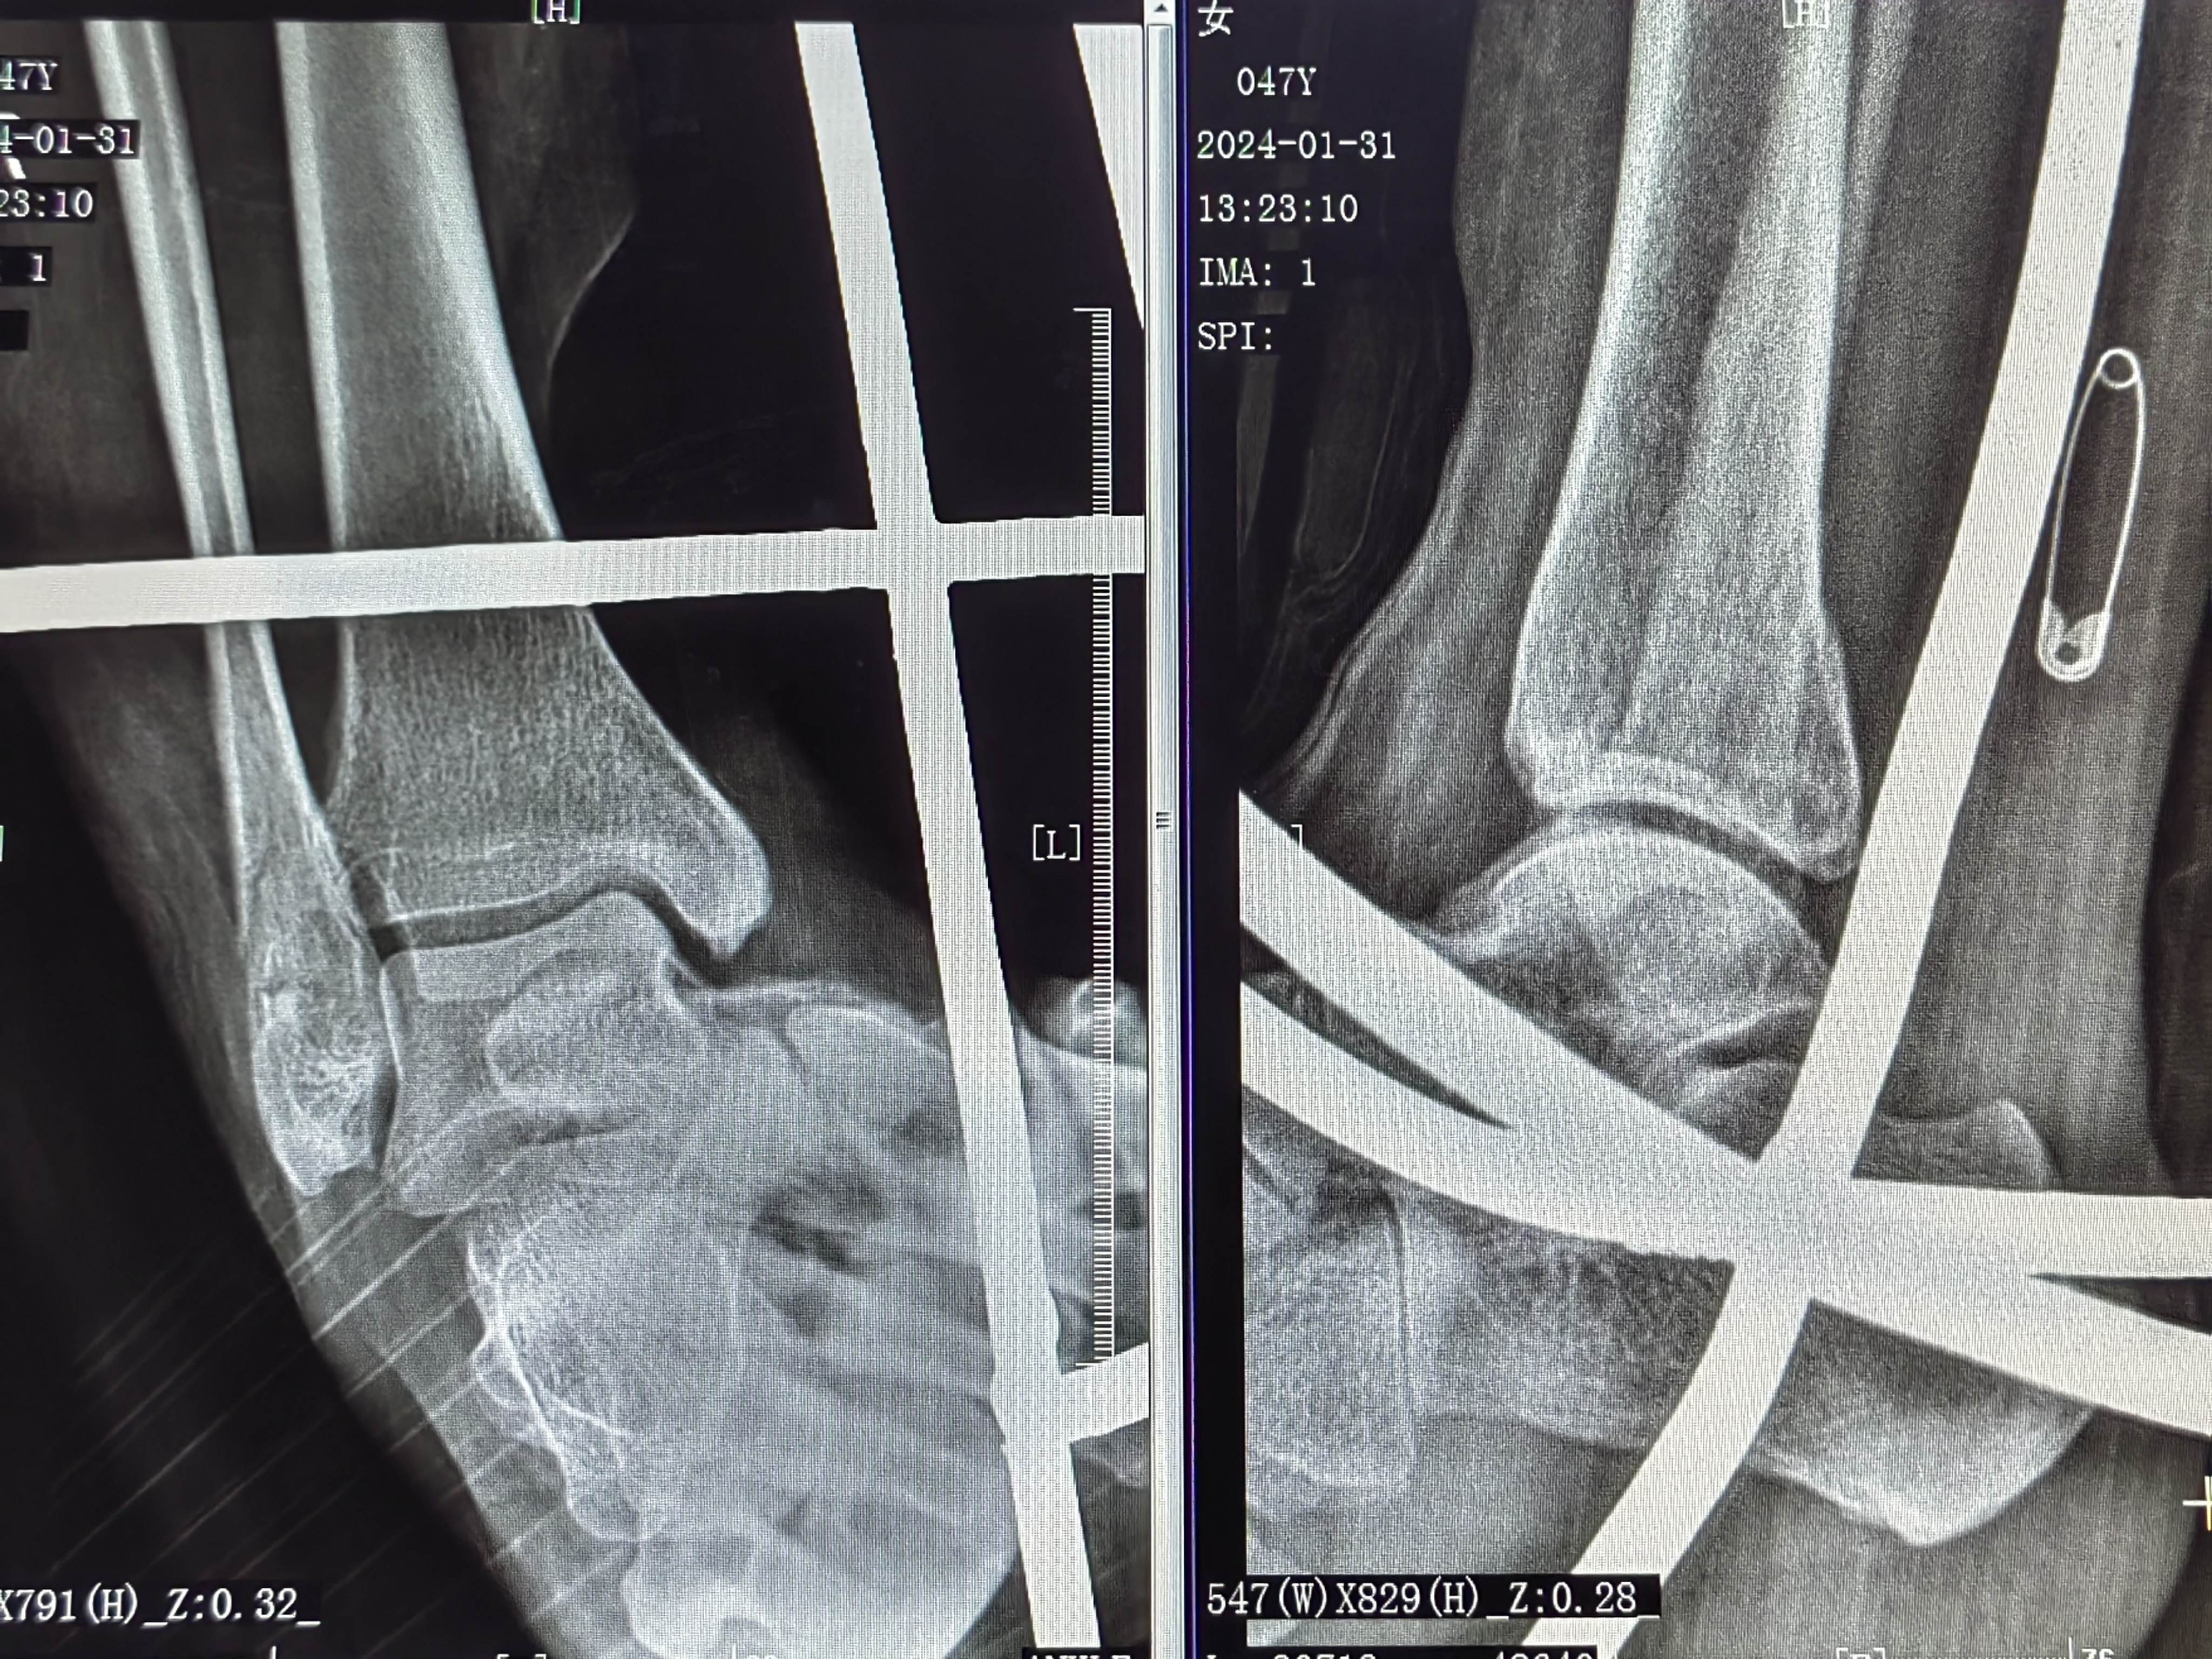

患者宋女士,47岁,右踝扭伤肿痛活动受限2小时于2024-1-30来诊。

初步诊断:右踝关节骨折

治疗方案:闭合复位夹板纸壳靴外固定治疗